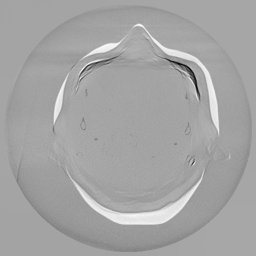

III-C Uncertainty analysis

Classical diffusion models reconstruct images by progressively denoising from an initial Gaussian noise image, a process that inherently introduces uncertainty due to random noise initialization. In contrast, I2SB directly learns a diffusion bridge between two sample distributions, effectively bypassing the need for random noise sampling and thereby reducing reconstruction variability.

To assess the uncertainty of our method, we performed multiple reconstructions using different random seeds. As shown in Fig. 3, the ground truth and representative sampled images are presented in Fig. 3(a) and (b–d), respectively. The mean reconstruction and pixel-wise standard deviation across runs are displayed in Fig. 3(e) and (f). Only minimal differences are observed between reconstructions, indicating that I2SB produces highly consistent results. These findings confirm that, compared with classical diffusion models, I2SB substantially reduces uncertainty across repeated reconstructions.